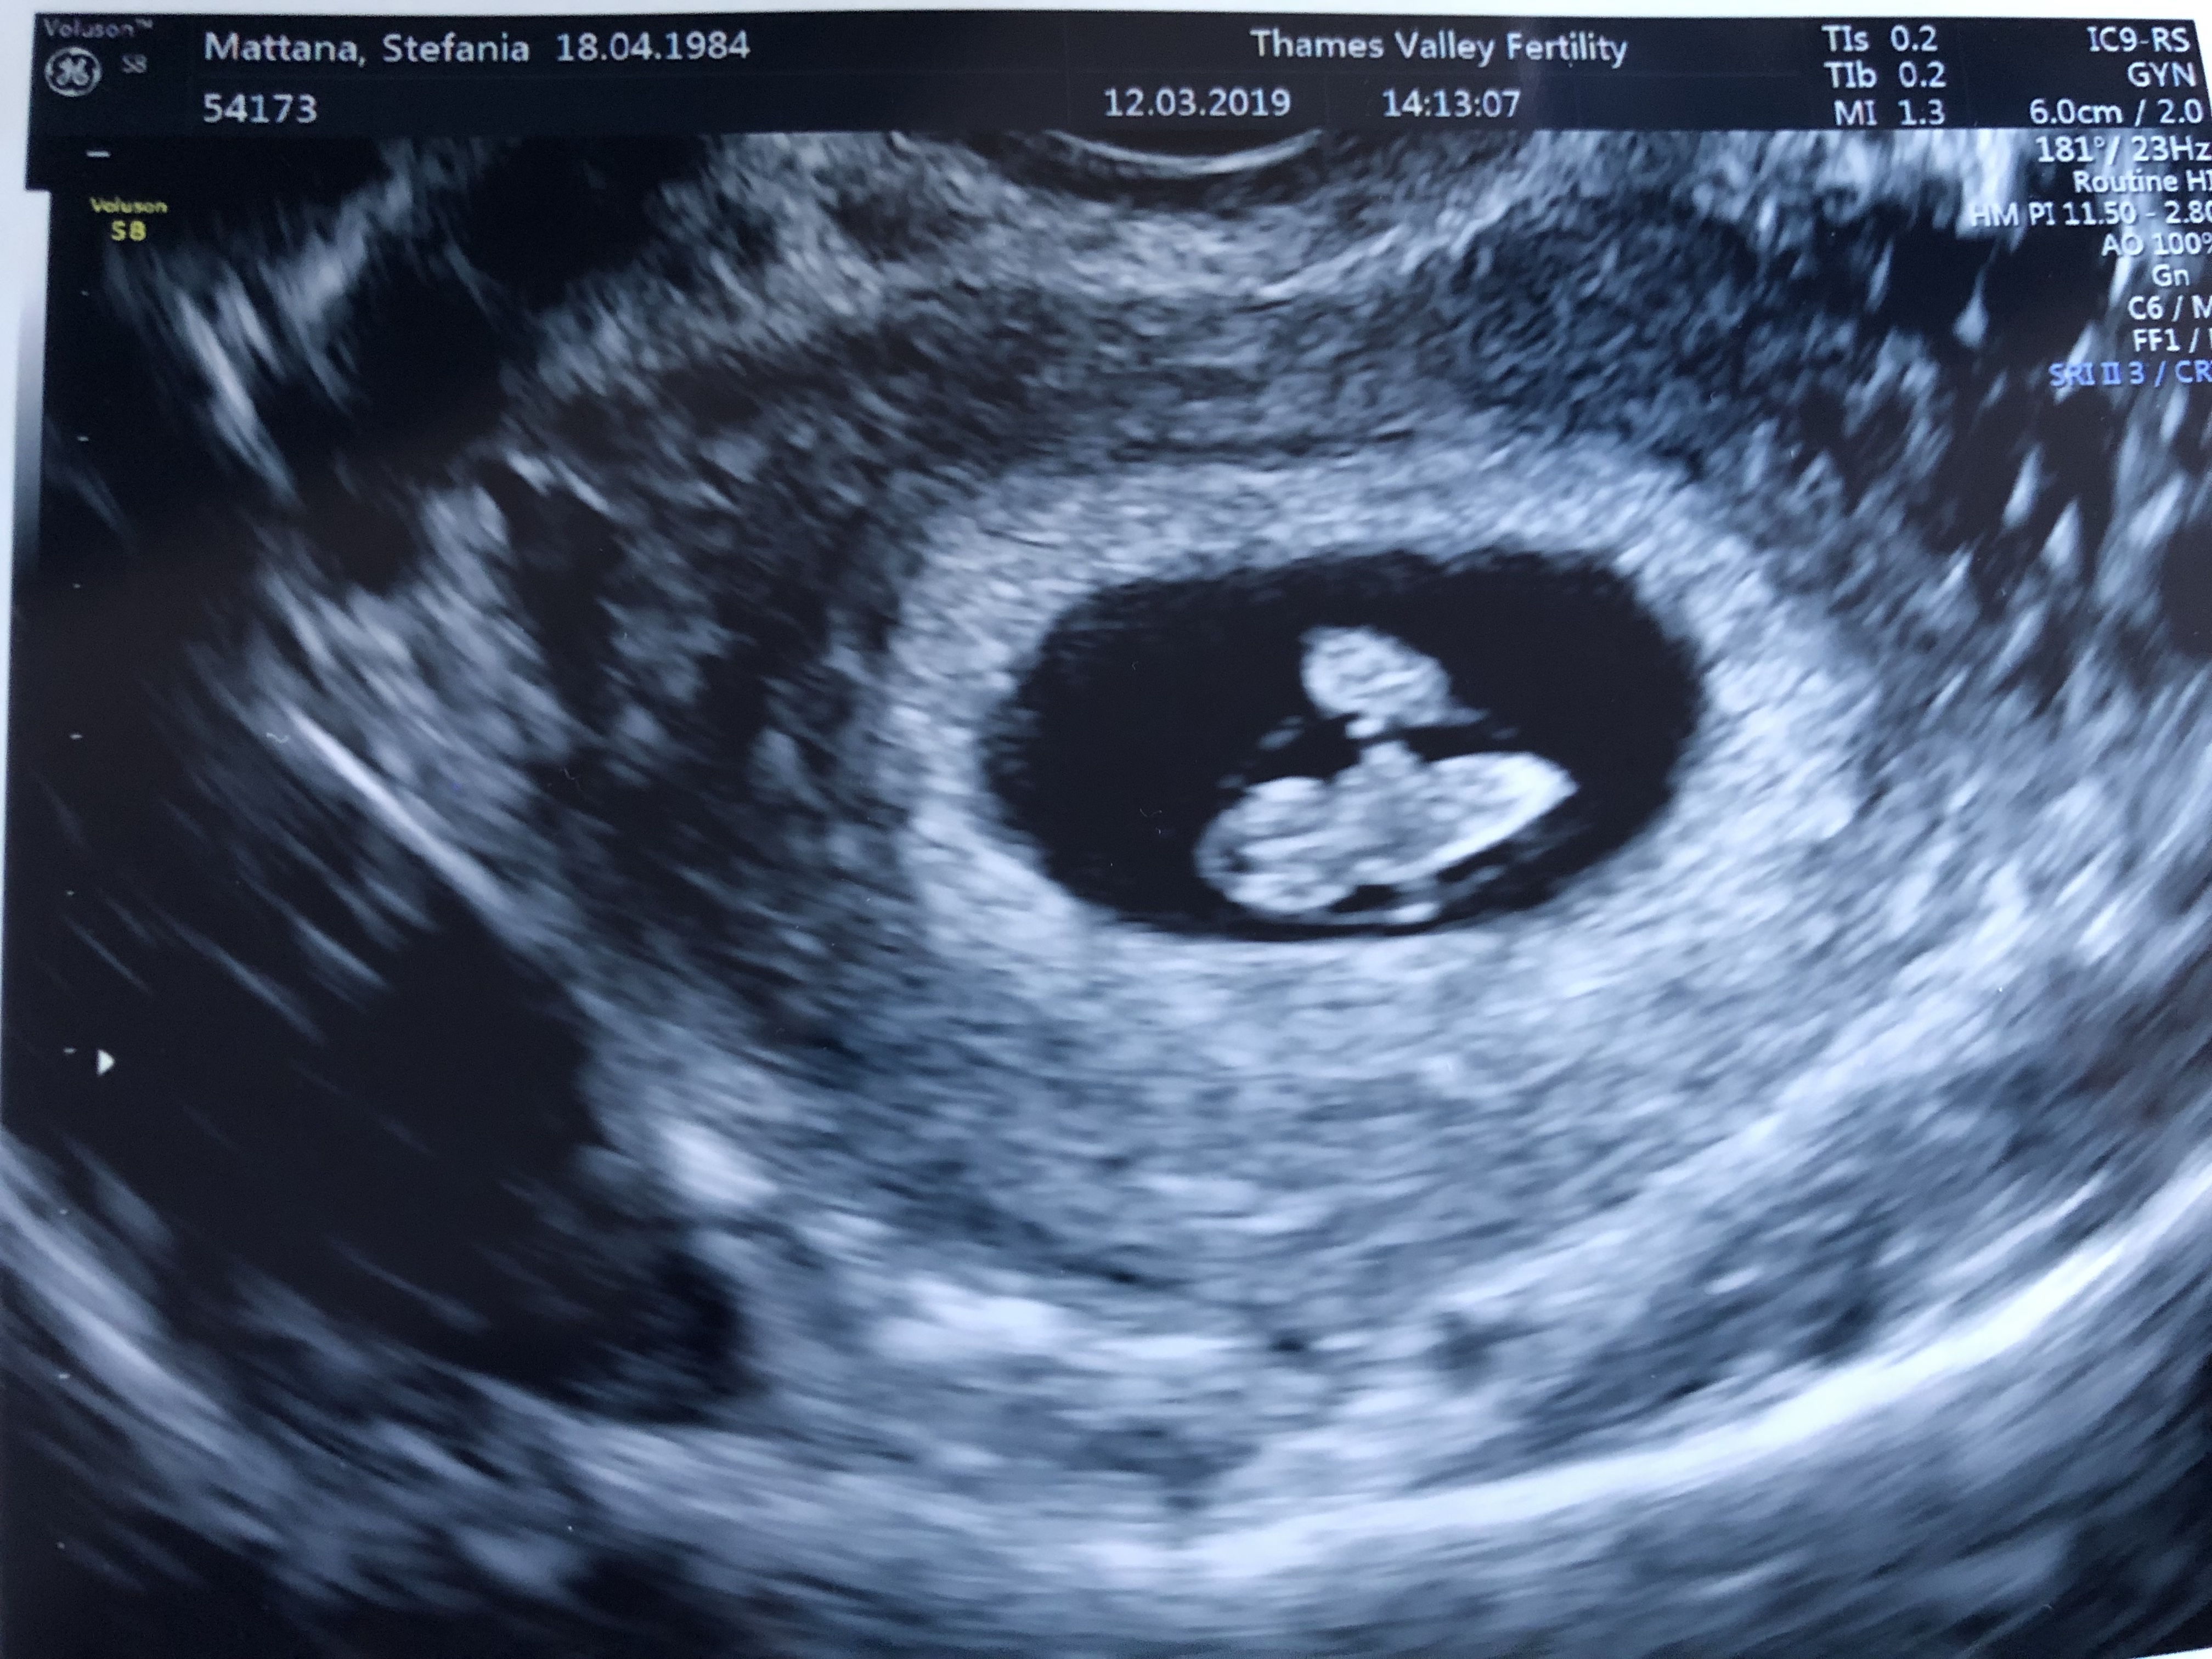

Don’t they look like a legit snowman here? Snow angel the hell out of it, Frosty!

The sonographer was so skilled – and Frosty was so well placed in the womb – that not only did she manage to see the heart beating, but also she made us HEAR it! This is kind of unusual as you can hear the heartbeat at around week 10/12.

It lasted only a bunch of seconds, but HOLY SHIT, this is happening for real.